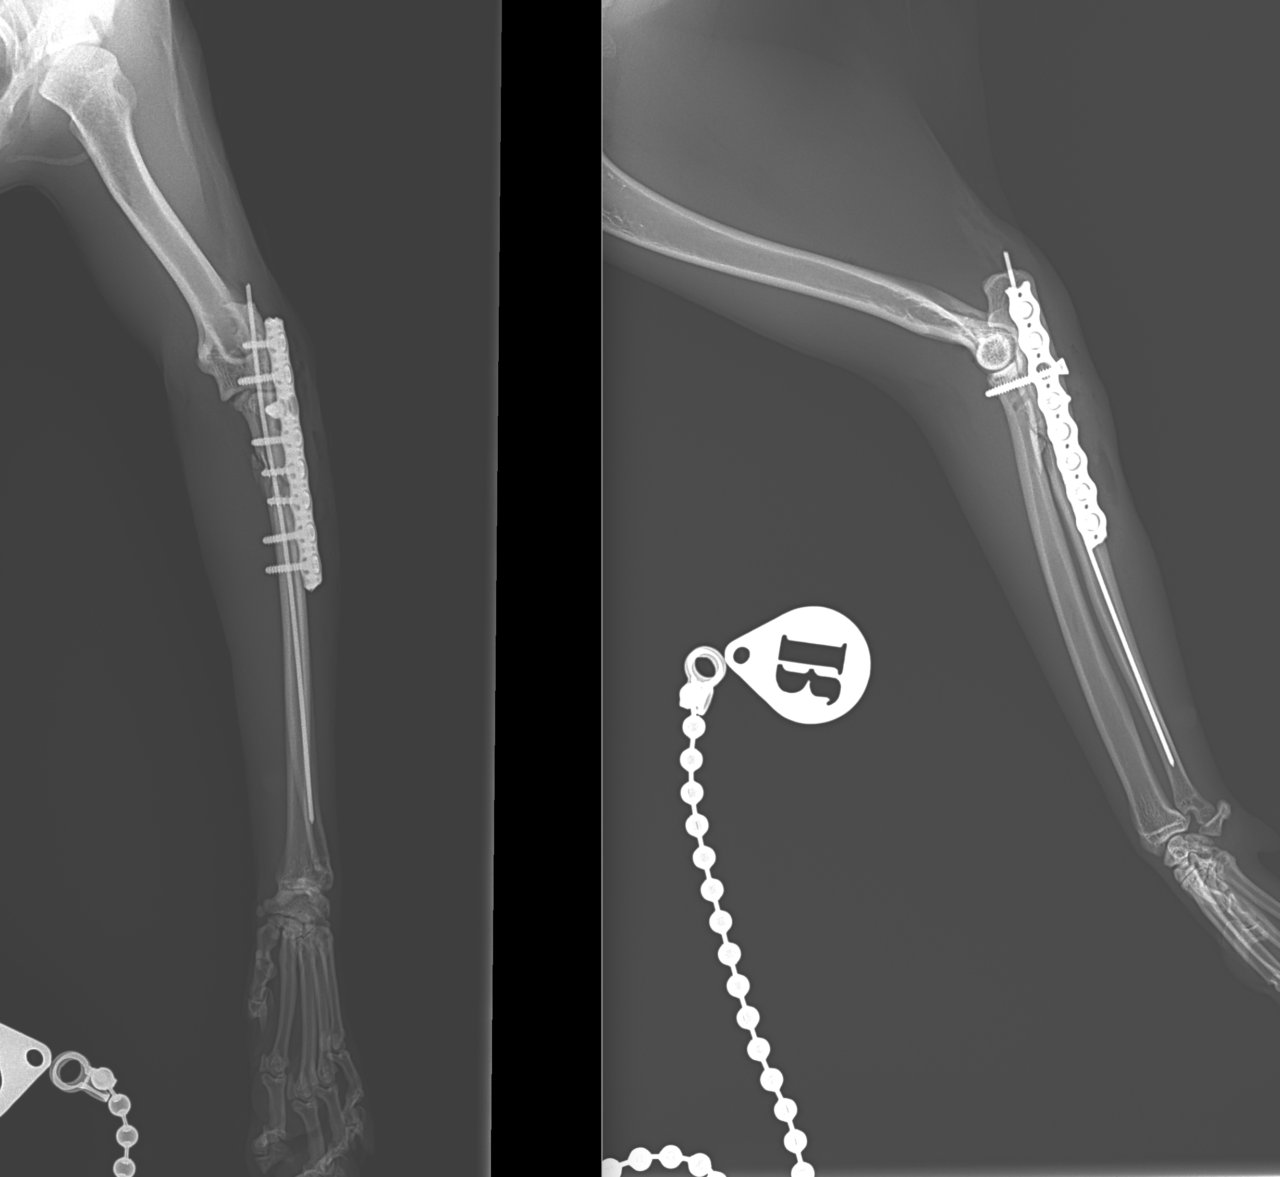

猫ちゃんがお家から居なくなり、探していたところお庭でうずくまって居るところを発見されました。かかりつけの動物病院で両側のモンテジア骨折と診断されました。(原因は落下事故と判明)外科的整復のため当院へ搬送されました。橈骨頭を整復したのち、尺骨にIM pinを刺入、2.0-Locking Plateで固定術を行いました。橈骨頭へ尺骨側からポジションスクリューで固定を併用します。このスクリューは約4週間を目安に抜釘を予定しています。